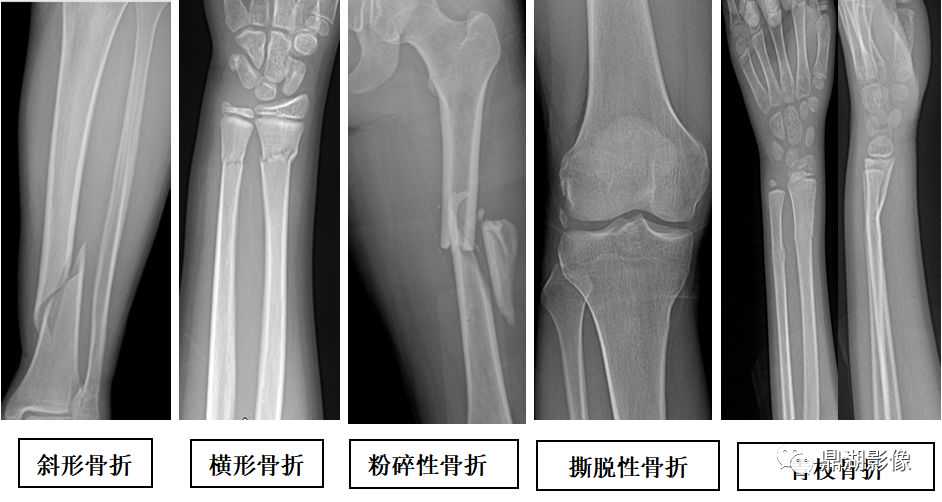

四肢骨折

骨折类型